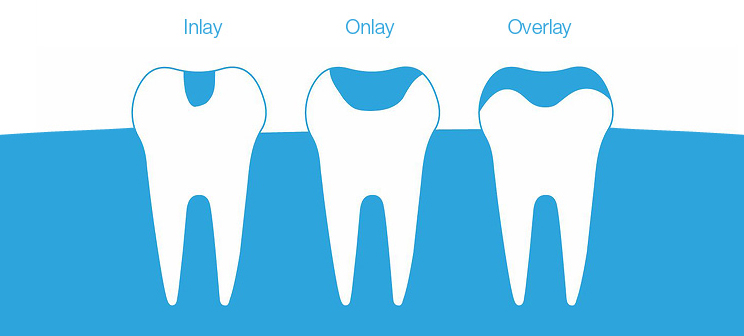

Inlays/Onlays

Apart from a simple filling, inlays and onlays are the most conservative option for restoring a tooth. Whether you have a larger cavity or your tooth has been chipped or broken, an inlay or onlay is a great way to restore the aesthetics, health and function of your smile. Inlays and onlays are used to supplement the natural tooth and fill in areas that have been decayed or damaged. Inlays repair damage contained within the cusp (outer ridge) of the tooth, while onlays are slightly larger and repair any damage that extends beyond the cusp.

Inlays and onlays require minimal removal of healthy tooth structure. Hence, they are a great option for patients who need a restoration, but don’t quite require a full crown.

With our advanced CEREC® same day technology, we can usually complete the whole process in a single visit! Read more about the benefits of CEREC® same day technology above.